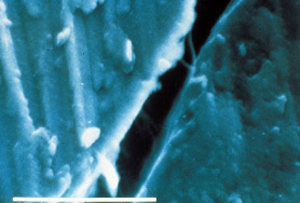

![]() チタンインプラントチタン-骨界面の電顕像。両者はムコ多糖体タンパクを介してわずかなギャップが存在し、ミクロレベルでは完全に接触していない。 |

HAインプラントHAと骨の界面にはCaが沈着し、両者は生化学的に直接骨結合する。これが“Biointeg ration”である。HAコーティングインプラントの意義はまさしくこのBiointegrationによるものと考えられる。 |